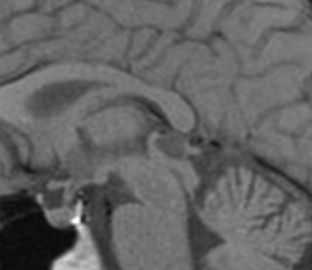

МРТ головного мозга. Т1-взвешенная сагиттальная МРТ. Киста кармана Ратке.

Киста кармана Ратке представляет собой редко встречающееся образование из остатков эмбриональной эктодермы (щель Ратке), расположенное между долями гипофиза. Выявляется в любом возрасте, но чаще в 50-60 лет. Клинические проявления связаны с масс-эффектом. При МРТ головного мозга выявляется небольшая (3-5мм) киста с четким контуром, без отека вокруг, однородная по структуре. Сигнал на МРТ головного мозга зависит от содержимого. При серозном содержимом сигнал типично жидкостный, при мукоидном киста светлая на Т1-взвешенных МРТ головного мозга. В 70-80% случаев внутри кисты выявляется неконирастирующийся узелок («пятно») - признак патогномоничный для кисты кармана Ратке. В редких случаях киста достигает больших размеров и даже выходит за пределы седла. Стенка кисты иногда усиливается при МРТ головного мозга с контрастированием. Дифференциальная диагностика при МРТ головного мозга должна проводиться с арахноидадьной и эпидермоидной кистами, тератомой, кистозной аденомой гипофиза и краниофарингиомой. Иногда при МРТ головного мозга киста кармана Ратке напоминает “пустое” турецкое седло. При маленьких размерах кисты ее на до дифференцировать на МРТ с микроаденомой гипофиза.